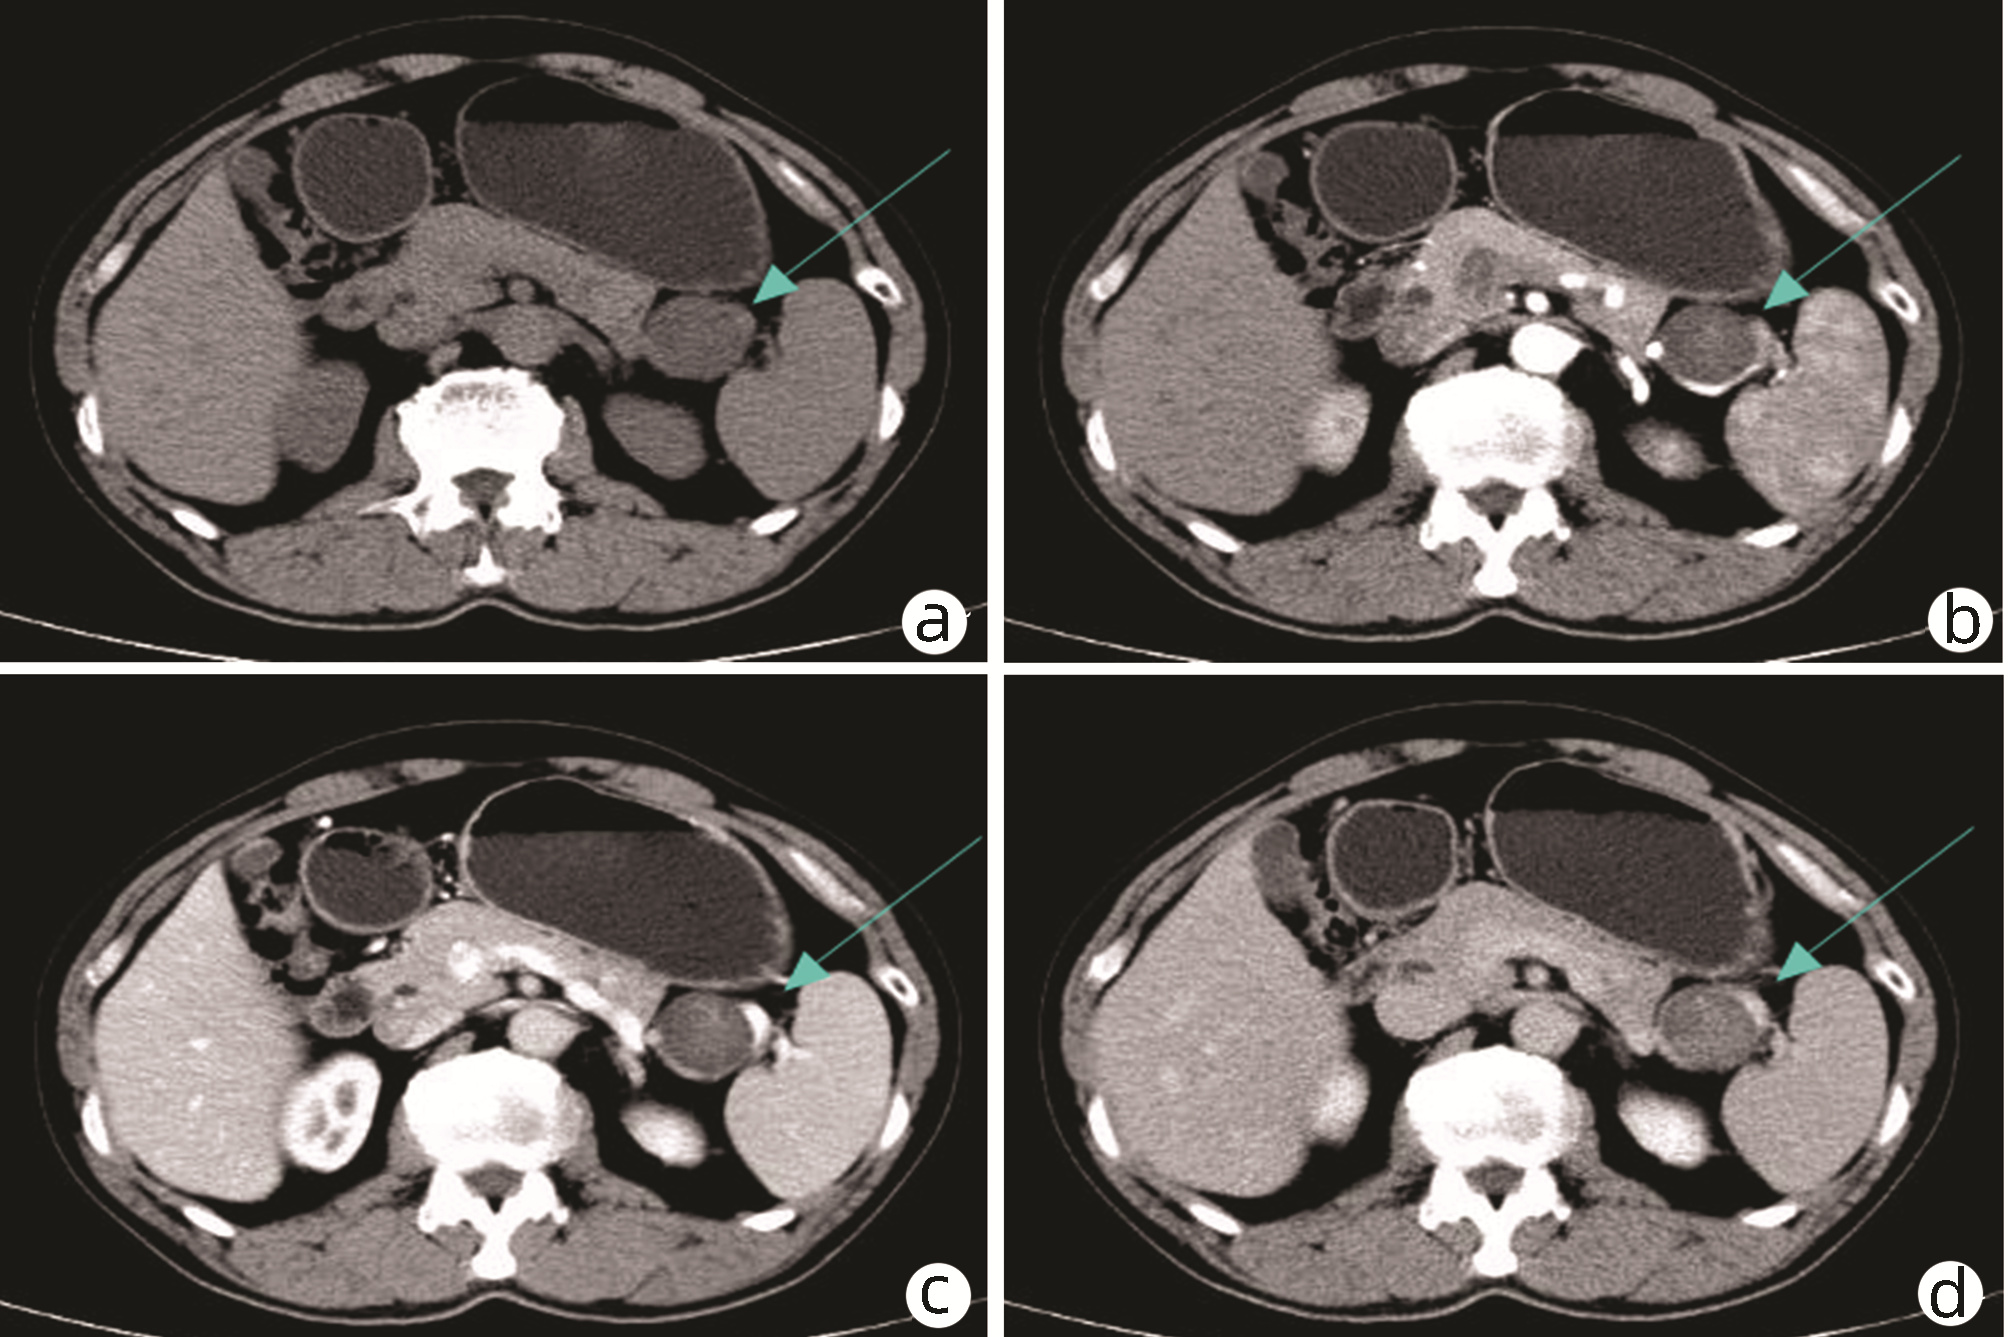

Late-onset diaphragmatic hernia after microwave ablation of hepatocellular carcinoma: A case report

Xiaodong WANG, Yurong ZHANG, Xiaoning ZHU, Ding ZHENG, Jing WANG

2022, 38(8): 1875-1877. DOI: 10.3969/j.issn.1001-5256.2022.08.029

Abstract(834) HTML (321) PDF (2572KB)(47)

Abstract: